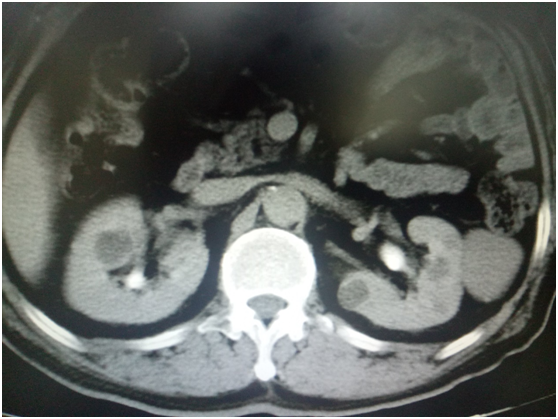

付大爷最近几个月可谓是苦不堪言啊,岁数来到了70,好像哪哪都不舒服了。这不,除了腰酸,还有,男人特有的,“蛋疼”,下腹部及阴囊反复疼痛坠胀不适。终于他下定决心,来到了杭州市第一人民医院。接诊他的是泌尿外科主任医师邓刚。邓刚主任检查病情后已经有了初步判断,在做了B超和CT证实后,付大爷的病算是明了了——双侧肾囊肿,还有双侧的精索静脉曲张。这与他的症状很相符。

尽管这两个病都是泌尿外科常见病,手术对于邓刚主任医师来说也都是常规操作。如果按常规手术,那么付大爷需要先分别做肾囊肿手术,然后再二次行精索静脉曲张手术,但因为都是是双侧手术,即使采取微创的腹腔镜手术,两边两个手术加起来,总共需要进行的腹腔镜打孔数有9个之多!付大爷别的没啥,就是胆小,一听手术,早已吓得已经面无表情了,何况要多次手术,身上又会“千疮百孔”呢?邓刚主任医师在在仔细分析病情,反复研究手术方案后,决定一次手术解决所有问题!邓刚主任医师带领医疗团队为付大爷计划并实施了经腹腔镜下双肾侧囊肿去顶减压术+双侧精索静脉曲张结扎术。满打满算,可是做了四个手术呢!而付大爷腹腔镜的手术置孔仅有4个,使用3个穿刺器,就迅速圆满地完成手术,真真正正的做到了微创!这可真是“外科医生巧手术,一箭多星除病患”。而且手术中,发现肾囊肿液炎症浑浊,精索静脉曲张的程度也比较严重。这次的手术可谓“及时雨”。